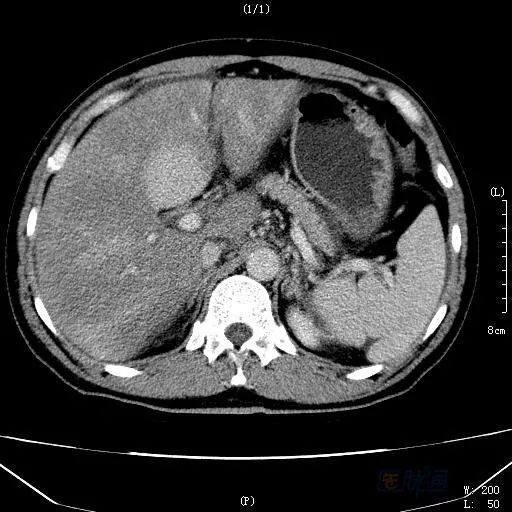

男性,45岁,近半月来出现“腹胀、黄疸、食欲下降”,于本地三甲综合性医院诊治。肝功能:TBIL 200μmol/L,ALT 1200U/L,ALP 201U/L,GGT 332U/L;B超发现大量腹水,肝脏占位性病变;增强CT同样示肝脏占位性病变(见图1),不排除恶性病变,考虑肝细胞癌可能性大!病人收住普通外科,准备手术。经过约半月的保肝,利尿等治疗,腹水明显减少,但肝功能仍然异常。

图1 延迟期扫描

HSOS的CT平扫显示为肝实质密度不均匀减低,腹水、肝脏体积增大等表现,此与肝脏淤血及肝细胞变性、坏死相关。由于窦后性门脉高压造成门脉期强化峰值减低或延迟;肝脏淤血及肝细胞变性、坏死则造成无或低灌注区域;另外,由于尚存相对正常的肝脏组织,而这类组织的门静脉灌注相对正常,便产生了正常肝组织与受损组织之间的强化差异;肝脏显示特征性的斑片样、地图样强化和低灌注区。延迟扫描:由于门脉强化峰值延迟、门静脉血流灌注增加,出现低密度区域减少和增强区域增加,肝脏密度趋于一致,而如果延迟后仍为低灌注的区域,则提示这部分的肝脏组织坏死严重。